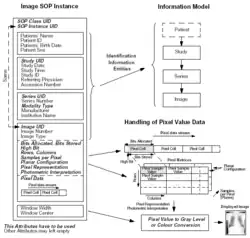

The Digital Imaging and Communications in Medicine (DICOM) standard delineates a sophisticated structural schema that integrates medical imaging data with pertinent patient identifiers into unified data sets, analogous to the embedded metadata in JPEG images. Such DICOM entities are constituted by a multitude of attributes, notably encapsulating pixel data, which in certain imaging modalities, corresponds to discrete images or, alternatively, an array of frames exemplifying kinetic or volumetric data, as observed in cine loops or multi-dimensional scans in nuclear medicine. This architecture accommodates the assimilation of intricate, multi-faceted data into a monolithic DICOM file. The standard accommodates a spectrum of pixel data compression algorithms, including but not limited to JPEG and JPEG 2000, and provisionally allows for holistic data set compression. DICOM specifies three encodings for data elements, with a predilection for explicit value representations, barring specific exceptions as elaborated in Part 5 of the DICOM compendium. Uniformly applied across diverse applications, the file manifestation customarily incorporates a header that houses essential attributes and data on the originating application.